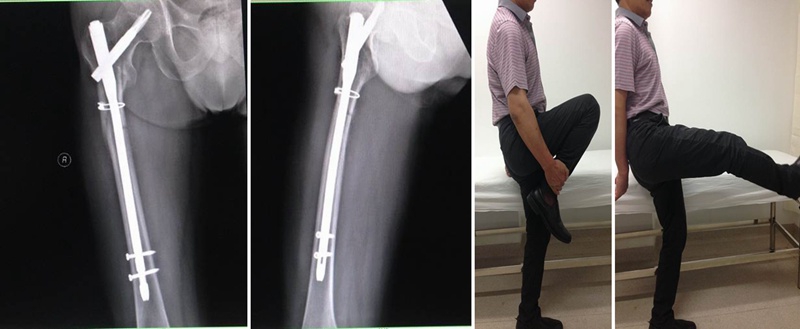

钱XX,女,43岁

术后